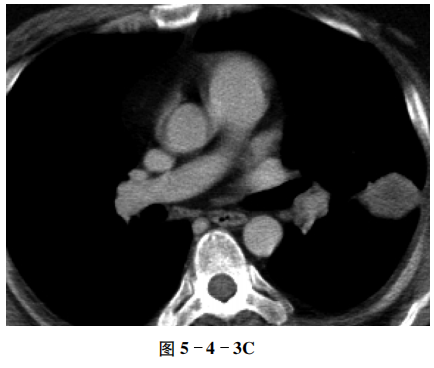

【CT征象】 左肺下叶背段可见一球形密度增高影,边界欠清,可见少许短粗条索影;重组冠状位图像可见其肺门侧支气管通畅;纵隔窗病灶呈软组织密度;增强扫描病变呈不均匀较明显强化(图5-4-3A~C)。

【重要征象】 球形密度增高影,边界欠清,病灶内侧支气管通畅;增强扫描呈较明显强化。

⑤ 增强扫描病灶呈渐进性明显强化。